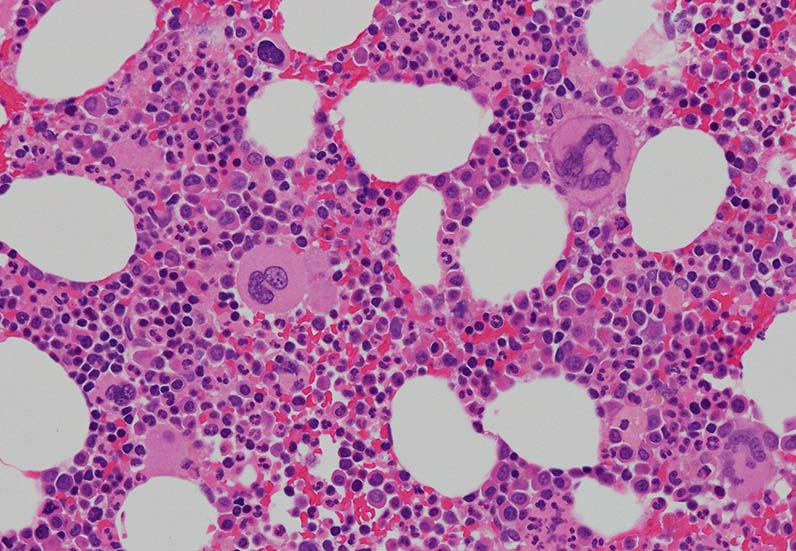

骨髄組織所見

cellularity60-70%ほどの過形成髄. ETは通常, 正形成髄から軽度の過形成髄, まれに低形成髄のこともある. 本例は軽度過形成傾向なcellularity. 巨核球数増加が目立つほか, stag-horn, cloud-likeといわれる核をもつ大型巨核球が認められる他, 小型で若い巨核球も増加している. ETでは, 連続する巨核球分化が認められる. 顆粒球系細胞増多が認められる.

Mgkの凝集所見があるが, 5-6個の緩やかな凝集で, loose clusterと呼ばれる. (Dens cluster:9個以上[数は厳密]の密なcohesiveな増殖は線維化がない場合, prefibrotic myelofibrosisの重要な所見になる)